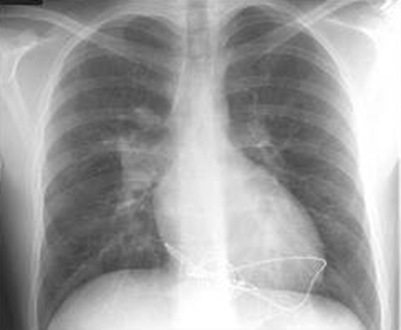

9. CXR: boot shaped heart, decreased pulmonary vasculature, right aortic arch

image Boot-Shaped Heart - Tetralogy of Fallot, tricuspid atresia